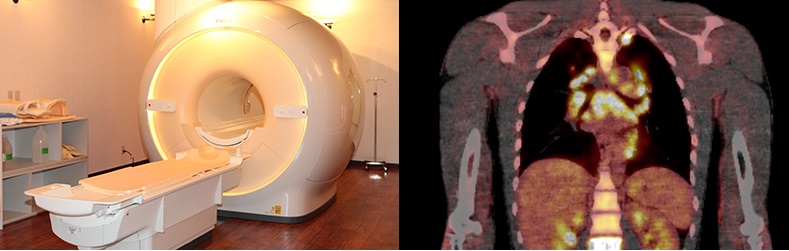

画像診断科では、院内の全ての科の患者様を対象とした画像診断を受け持っています。診療は単純写真、消化管造影検査、CT、MRI、血管造影、核医学に大別されます。CTは5台、MRIは6台で、毎日多数の検査を行っています。待ち時間を少なくするため原則として予約制をとっていますが、緊急検査にも対応していますので、即日の検査、診断が可能です。また、緊急血管造影にも対応しています。

近年画像診断装置の開発は著しく、心臓のような拍動している臓器でもCTやMRIにて鮮明な画像を撮ることができるようになりました。 当院では最新の128列デュアルソースCTを用いて冠動脈CT検査(CT coronary angiography: CTCA) を行っています。ヨード造影剤を静注しながら心電図同期下に撮影を行い、ある同一心時相の画像を再構成し静止画像として描出し評価します。128列デュアルソースCTでは、冠動脈のような拍動する細い血管でも高精細な画像が得られるため、冠動脈造影との比較でも高い診断能を有しています。狭窄有無の評価のほか、動脈硬化によるプラークの性状評価もCT値から予測することも可能です。実際の撮影は呼吸停止10秒以下で冠動脈全体の範囲が撮影でき、検査の準備も含め15分前後で検査が終了します。外来の通常検査枠で行っていますが、医療連携室を介して直接近隣の医療施設からの紹介でも検査可能です。

また最新鋭の装置を用いて心臓MRI検査も行っています。全体の撮影自体は40分から1 時間とやや長いですが、1 回の検査で心臓の形態評価、心機能評価、心筋性状の評価が行えます。心筋梗塞の患者では心筋梗塞の範囲が描出できるため、心筋のバイアビリティの診断も可能です。そのほか、心筋症、心筋炎などさまざまな疾患の診断が可能で、心不全の原因評価、治療効果の評価などにも用いています。また造影剤を用いずに冠動脈を撮影する方法もあり、喘息や腎不全など造影剤が使用できない患者さんに有用です。

CT coronary ngiography

正常の左右冠動脈

Cardiac MRI

遅延造影MRIによる心筋梗塞の診断

左室短軸画像、前壁中隔梗塞